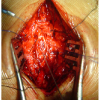

At 1st metacarpophalangeal joint full flexion is possible (Power-5/5), but extension was unable to do (Power-0/5) (Fig. 3). Sensations were reduced over the 1st dorsal web space (Grade – 0/2). X-ray was taken and diagnosed as Grade IIIa open the left Monteggia fracture–dislocation (Bado’s Type – III) with PIN palsy (Fig. 4). Emergency wound debridement + Open reduction internal fixation with plate osteosynthesis of the left proximal 1/3rd ulna shaft fracture was done, 8 h after the injury (Fig. 5). Checked under C – Arm and found that radial head was relocated and was in correct position. Above elbow POP application was applied in supination position. Immediate post-operative day 1, there was no improvement in the sensory and motor power of the thumb. The patient was advised to continue POP application for 4 weeks and was given supportive medication Tab. Neurobion forte once daily for 4 weeks and advised to use dynamic cock-up splint. The patient was followed up and examined weekly once. After 4 weeks of fixation, on examining, the patient sensations were improved fully (grade – 2/2) and the motor power improved to 3/5. POP was removed and patient was advised to use dynamic cock-up splint. After a total of 6 weeks, on examining, the patient sensations were fully intact (2/2) and motor power improved to 5/5 (Fig. 6). Fracture union was seen on 3rd month post-operative X-ray and full range of movements of elbow obtained without any major complications noted.